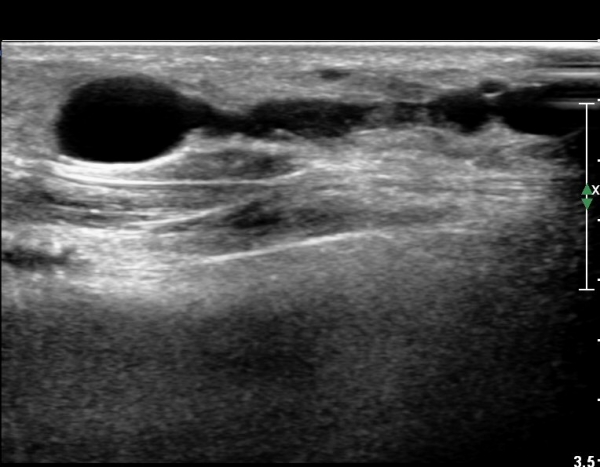

³¶Á¾À» Á¾´Ü¸éÀ¸·Î °üÂûÇÏ´Ï ³¶Á¾ÀÌ ¸»´Ü °æ°ñºñ°ñ°üÀý¿¡¼ À¯·¡µÊÀÌ È®ÀεȴÙ(»çÁø 9).